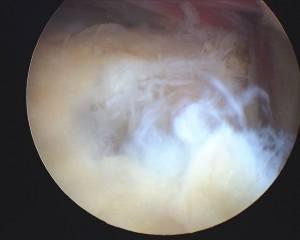

Rotator cuff tear

Tear debrided